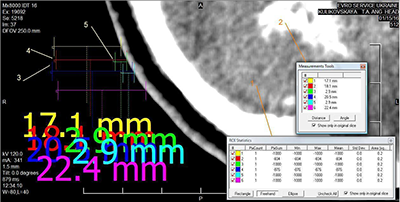

The interpretive bias test procedure referred to Woud et al. [43]. Participants completed 9 ambiguous scenario tasks. The procedure for each scenario is shown in Figure 1: 1) Presentation of the ambiguous scenario, with the last character of the final sentence omitted. 2) Participants were asked to fill in the missing character according to the context. 3) Feedback was provided: if correct, the complete character was displayed in green; if incorrect, a red error message appeared, prompting participants to retry. 4) After each scenario, a question asking whether participants understood the scenario’s meaning was presented, and participants responded “Correct” or “Incorrect.” 5) The ambiguous scenario and its two interpretation target sentences were presented again, and participants rated the fit between each target sentence and the scenario.

(1) Measure of interpretive bias: Referring to the experimental materials used in a series of alcohol related interpretive bias studies by Woud et al. [42, 43], 24 smoking related ambiguous scenarios were compiled (each with 2 interpretation target sentences). Thirty postgraduate students majoring in psychology rated the scenarios on theme relevance, interpretive fluency, and valence, and provided revision suggestions, leading to the final selection of 9 ambiguous scenarios. Each scenario was paired with two interpretation target sentences: one smoking related and one smoking unrelated. For example, the scenario was: “You walk restlessly in the room. You are dissatisfied with the current situation you have a backlog of work, and now you’ve lost your wallet. You just want to forget all the…” The two interpretation target sentences were: “You want to forget all your troubles and decide to smoke a cigarette” and “You want to forget all your troubles and decide to go for a run.” Participants were asked to rate the degree of fit between the behavior described in each interpretation target sentence and the scenario (1=Very inconsistent, 4=Very consistent).